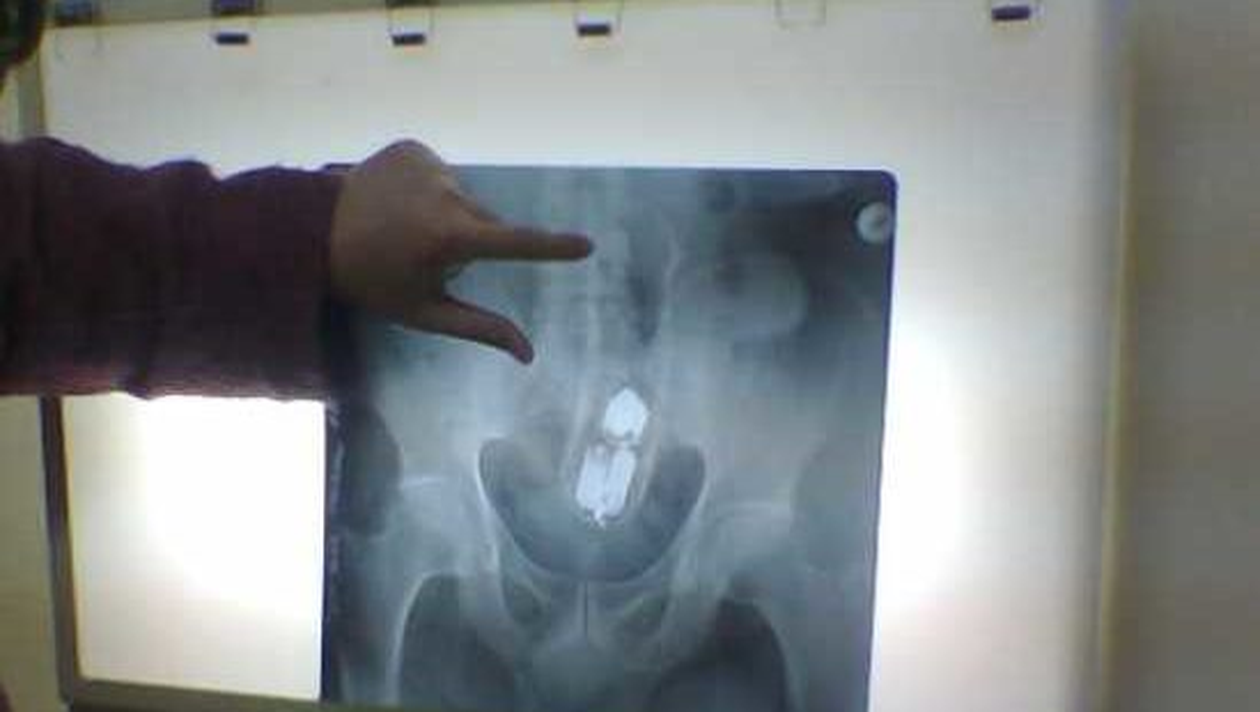

Întîmplare șocantă în județul Olt, comuna Brâncoveni, acolo unde un tânăr de 23 de ani a avut nevoie de intervenție chirurgicală de urgență după ce a ajuns la spital cu un deodorant în… anus. Pacientul sunase, în prealabil, la numărul de urgență 112, spunând că are dureri foarte mari în zona respectivă.

Medicilor nu le-a venit să creadă atunci când au observat că tânărul avea blocat în anus un tub de deodorant. Din cele declarate de el, se afla acasă cu iubita și s-a așezat din neatenție pe tubul respectiv. Ulterior, timp de nu mai puțin de 3 ore, ar fi încercat să rezolve singur situația neplăcută și periculoasă. Primarul din localitatea Brâncoveni spune că tânărul face parte dintr-o familie defavorizată, dar precizează și că – așa cum spus mama tânărului – acesta și-ar fi introdus tubul în anus, iar apoi nu a mai putut să îl scoată.